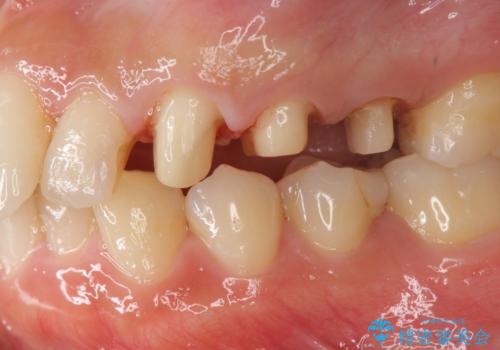

- 歯ぐきの腫れや、歯の内部が黒く見えることからの虫歯の治療を求めて来院されました。

虫歯が大きかったことから、神経の温存はできたものの歯ぐきよりも深い虫歯の問題を解決するため、部分矯正治療を併用したセラミック治療を行うこととしました。

当初、歯ぐきよりも深い虫歯の存在や、歯のポジションに問題がありましたがマルチブラケットを用いた部分矯正で行うことで歯の挺出同時に適切な位置へと歯を移動させ、歯周環境を整えたセラミック治療を行うことができました。